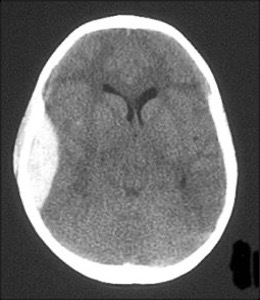

AGE ?

A

70-80

SHRINKED

ALOT MORE FLUID ABLE TO MOVE AROUND.

CONSIDERING HEAD TRAUMA THE BRAIN CAN BOUNCE WHICH CAN BE DANERGOUS.

contrecoup injury